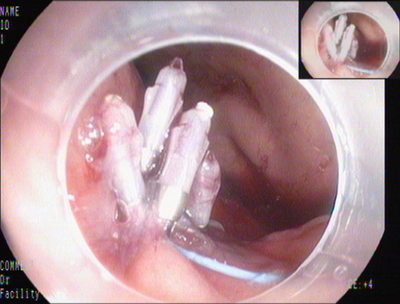

胃腔内切除的瘤体标本

钛夹缝合

分割后瘤体标本

复原的瘤体标本

2014年7月4日,田俊斌医师施行全身麻醉,李雪荣、左爱丽护师等为手术护士,邹百仓主治医师、张莉主治医师施行EFTR手术。胃镜下见胃底体交界前壁见巨大粘膜下肿瘤,暴露于胃腔的瘤体大小约3.0×4.0cm,表面光滑,中央凹陷。粘膜膜下注射后,环形切开瘤体周围粘膜,剥离瘤体周围粘膜下层,中央与肌层紧密连接,并向腔外生长,全层切开瘤体周围肌层,完整切除瘤体,可见腹腔脏器及网膜组织,钛夹尼龙圈荷包缝合切口,尼龙圈脱落,后用钛夹夹闭缝合切口,创面无渗血。由于标本较大坚硬无法完整一次取出,用圈套器将瘤体分切成5块,分块取出,拼凑复原瘤体形态,测量大小4.0×5.0cm。术后4天胃镜复查:胃壁切口溃疡形成,无出血及穿孔,嘱患者进食流质饮食。病理结果:胃底间质瘤,中、低度恶性风险,向神经纤维瘤发展。术后1周出院。